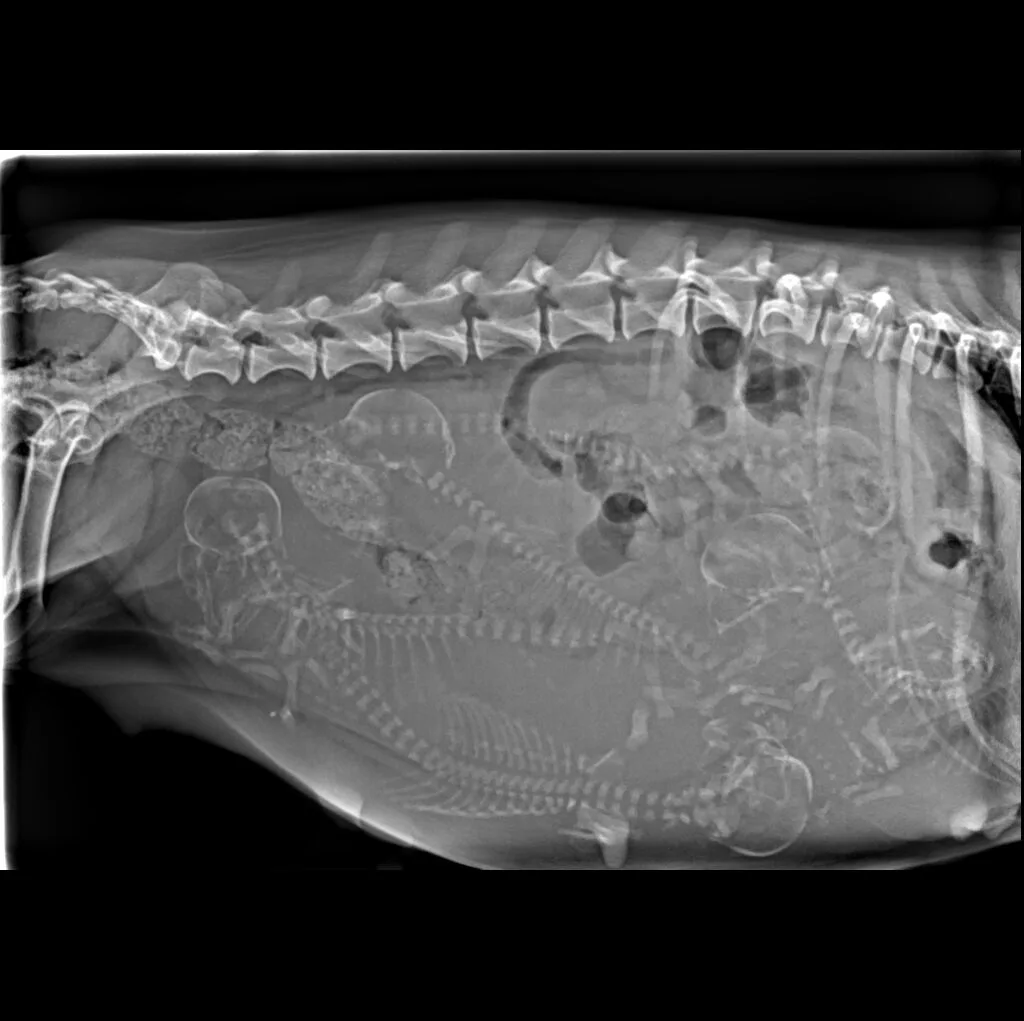

At Grand Ave. Pet Hospital, we utilize digital radiography to diagnose and monitor a wide range of medical conditions in pets. Digital X-rays provide clearer images, faster results, and safer radiation levels, ensuring the best possible care for your furry companion.

Digital radiography offers superior imaging quality and precision compared to traditional X-ray techniques. It allows us to detect hidden health issues early, leading to faster and more effective treatments.

🔹 Lameness & Joint Issues – Identifying fractures, arthritis, and mobility concerns

🔹 Cardiac & Respiratory Conditions – Evaluating heart disease and lung disorders

🔹 Abdominal & Gastrointestinal Issues – Detecting obstructions, tumors, or organ abnormalities